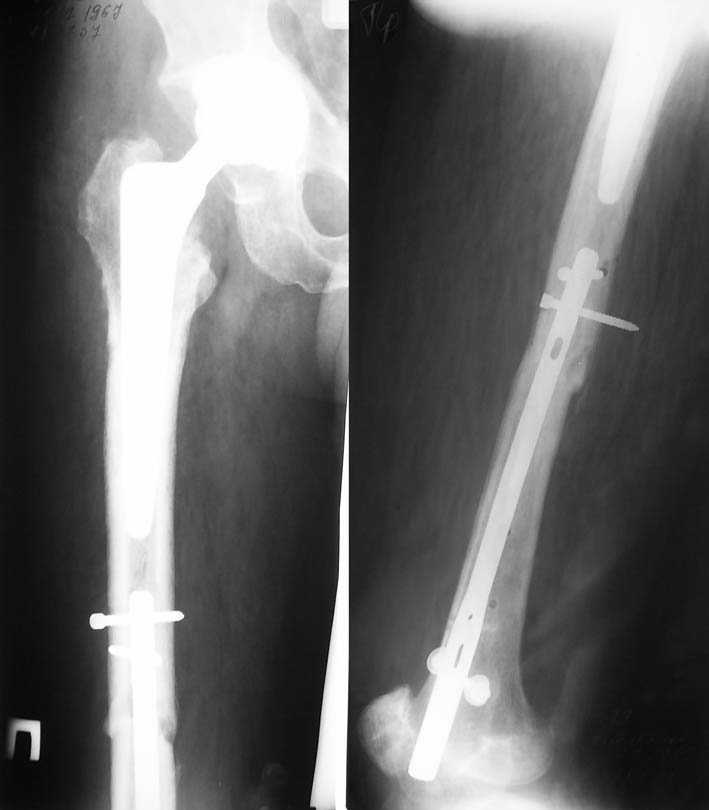

Несмотря на пессимистические прогнозы, у молодых

коррегирующая вальгусная остеотомия является более

приемлемым.

Представленные случаи доказательства тому, что еще

имеется резервы на восстановление даже у 5-6 месячных ложных суставов шейки.